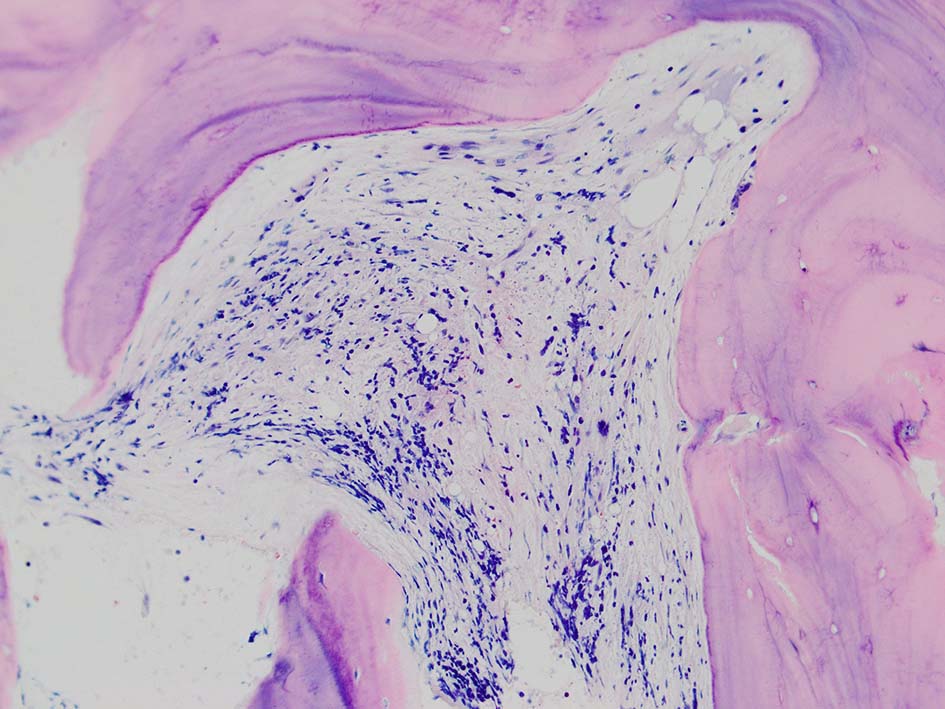

骨髄壊死(BMN)は,造血性骨髄(BM)の髄質間質と骨髄組織の広範囲な壊死を特徴とするユニークな臨床病理学的病態であり、無定形の好酸球性背景、由来不明瞭な壊死細胞、皮質骨の温存が認められる.*1

骨髄生検組織では骨梁間に壊死に陥った細胞の凝固壊死像が確認できる. 本例では脂肪細胞は消失せず形態が残っている.壊死のあとには, 髄腔に線維化をきたす. 上図には線維化を示し, 右端の図では壊死巣と線維化の境界が観察される.

本例ではviableな腫瘍細胞がハーバース管内(?)に認められた.(髄腔とハーバース管腔は解剖学的に同じ場所といえるのか?)